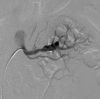

The commonest site of primary dissection involving the visceral vessels is renal arteries; however, spontaneous bilateral renal artery dissection is an extremely rare entity. Spontaneous renal artery dissection (SRAD) is rarely a cause of renovascular hypertension. Segmental arterial mediolysis is a rare arteriopathy of unknown etiology which is a nonatherosclerotic and noninflammatory condition. We report a case of a 51-year-old male patient with spontaneous dissection of bilateral renal arteries with clinical, laboratory, and angiographic findings consistent with segmental artery mediolysis. Early diagnosis and treatment of this condition will decrease morbidity and mortality.